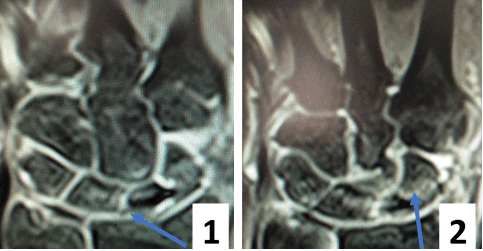

После операции лучезапястный сустав фиксировался иммобилизационной повязкой сроком на 4 недели. По окончанию срока иммобилизации пациентке была рекомендована постепенная разработка лучезапястного сустава, исключающая осевые нагрузки. Через 6 недель с момента операции пациентке было выполнено МРТ исследование для осуществления контроля положения восстановленной связки (рис. 5).

Рис. 5. МРТ исследование правого лучезапястного сустава. На МРТ сканах во фронтальной плоскости: 1) отмечается восстановление пространства между ладьевидной и полулунной костями, отчетливо видна связка; верифицируется биодеградируемый пин и якорный фиксатор в ладьевидной кости; 2) отмечается синовит лучезапястного сустава и отсутствие отека костной ткани ладьевидной кости